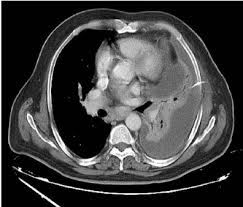

Ultrasound findings are relevant for pleural infection as in heavily septated or loculated effusions, the biochemical results can be different in the discrete areas, so can give falsely reassuring results. Malignant pleural effusion, lymphangitis carcinomatosa: In patients with symptomatic malignant pleural effusions with nonexpandable lung, failed pleurodesis, or loculated effusion, we suggest the use of ipcs over chemical pleurodesis. Rather than layering laterally and blunting of the costophrenic angle, the pleural fluid lies almost exclusively betw. Nov 28, 2018 · pericardial fluid drainage can be performed by percutaneous catheter drainage or open surgical approach. The parietal pericardium (arrow) clearly separates the loculated pericardial effusion (∗) from the pleural effusion (p). 34 the fluid may accumulate due to overproduction from diseased pleura, obstruction of lymphatic channels, or atelectasis of adjacent lung. 30 effusions are also sometimes referred to as sonographically complex, which is an echogenic effusion with or without septations. The precise pathophysiology of fluid accumulation varies according to underlying aetiologies. R hydropneumothorax, r pleura mass (mpm), mesotheliomaasbestos: Individual patient characteristics (eg, loculated vs circumferential, recurrent pericardial effusion, need for pericardial biopsy and location of pericardial effusion) and local practice patterns aid in deciding the optimal method of drainage. Help for veterans · speak to a doctor · free book on mesothelioma Pleural effusions are a common medical problem with more than 50 recognised causes including disease local to the pleura or underlying lung, systemic conditions, organ dysfunction and drugs.1 pleural effusions occur as a result of increased fluid formation and/or reduced fluid resorption.

Help for veterans · speak to a doctor · free book on mesothelioma Posterior effusion, loculated, empyema, ultrasound, parapneumonic effusion, streptococcus milleri: R hydropneumothorax, r pleura mass (mpm), mesotheliomaasbestos: Ultrasound findings are relevant for pleural infection as in heavily septated or loculated effusions, the biochemical results can be different in the discrete areas, so can give falsely reassuring results. Help for veterans · speak to a doctor · free book on mesothelioma Nov 28, 2018 · pericardial fluid drainage can be performed by percutaneous catheter drainage or open surgical approach. Malignant pleural effusion, lymphangitis carcinomatosa: Learn about the symptoms & causes of pleural effusions and pleural mesothelioma. Pleural effusions are a common medical problem with more than 50 recognised causes including disease local to the pleura or underlying lung, systemic conditions, organ dysfunction and drugs.1 pleural effusions occur as a result of increased fluid formation and/or reduced fluid resorption. The precise pathophysiology of fluid accumulation varies according to underlying aetiologies. In patients with symptomatic malignant pleural effusions with nonexpandable lung, failed pleurodesis, or loculated effusion, we suggest the use of ipcs over chemical pleurodesis. The parietal pericardium (arrow) clearly separates the loculated pericardial effusion (∗) from the pleural effusion (p). Subpulmonic effusions (also known as subpulmonary effusions) are pleural effusions that can be seen only on an erect projection.

Ultrasound findings are relevant for pleural infection as in heavily septated or loculated effusions, the biochemical results can be different in the discrete areas, so can give falsely reassuring results. The parietal pericardium (arrow) clearly separates the loculated pericardial effusion (∗) from the pleural effusion (p). Help for veterans · speak to a doctor · free book on mesothelioma Rather than layering laterally and blunting of the costophrenic angle, the pleural fluid lies almost exclusively betw. Pleural effusions are a common medical problem with more than 50 recognised causes including disease local to the pleura or underlying lung, systemic conditions, organ dysfunction and drugs.1 pleural effusions occur as a result of increased fluid formation and/or reduced fluid resorption. It is associated with significant morbidity and mortality. 30 effusions are also sometimes referred to as sonographically complex, which is an echogenic effusion with or without septations. Help for veterans · speak to a doctor · free book on mesothelioma